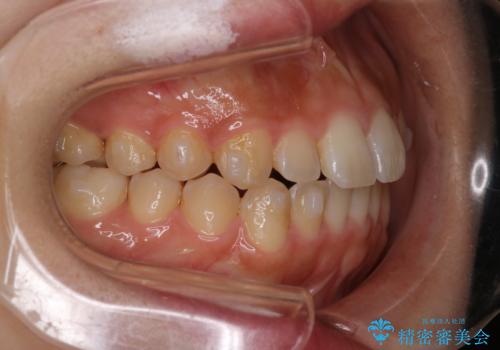

【インビザライン】がたつきをマウスピースできれいにしたい

- 20代女性

- 前歯の叢生を主訴に来院されました。非抜歯でインビザラインで治療をしました。

叢生はIPRをし、並べました。この患者様はオープンバイトだったため歯を並べる過程でかみ合わせも治しました。